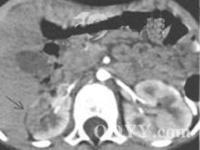

2、腎性高血壓可分為腎實質性高血壓和腎血管性高血壓:腎實質性高血壓多有腎臟病史,如急性腎炎,慢性腎炎,腎病綜合徵和慢性腎盂腎炎等。實驗室檢查多可發現異常,當診斷有困難時,需藉助腎穿刺明確診斷。腎血管性高血壓多見於30歲以下或55歲以上,突然發生惡性高血壓,或以往有高血壓史,突然轉為惡性高血壓者。同時要注意病史中是否有腰部外傷,腰背部或脅腹部劇痛,腹痛等。體檢時,頸部、腹部和脅腹部可有血管雜音。但上述徵象均無特異性,確診要靠腎血管造影等手段。